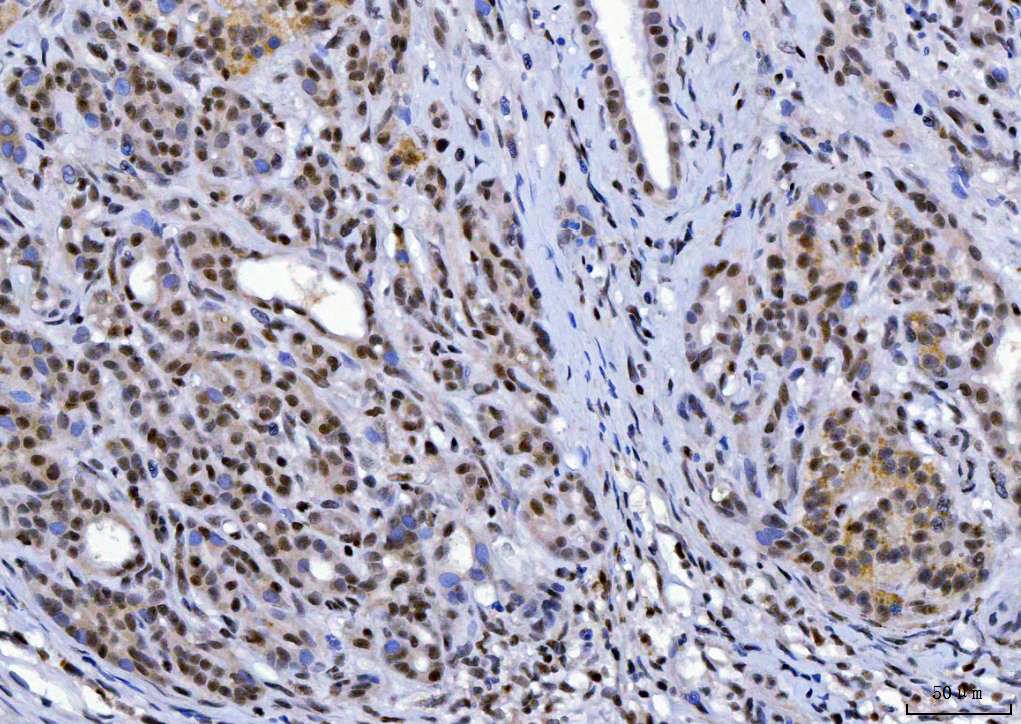

IHC analysis of YY1 using anti-YY1 antibody (M00833-2).

YY1 was detected in a paraffin-embedded section of human Pancreatic Ductal Adenocarcinoma tissue. The tissue section was incubated with mouse anti-YY1 Antibody (M00833-2) at a dilution of 1:200 and developed using HRP Conjugated mouse IgG Super Vision Assay Kit (Catalog # SV0001) with DAB (Catalog # AR1027) as the chromogen.